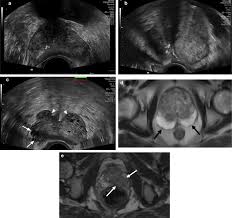

Cancers Free Full Text Correlation Between Intraprostatic Psma Uptake And Mri Pi Rads Of 68ga Ga Psma 11 Pet Mri In Patients With Prostate Cancer Comparison Of Pi Rads Version 2 0 And Pi Rads Version 2 1 Html

Cancers Free Full Text Correlation Between Intraprostatic Psma Uptake And Mri Pi Rads Of 68ga Ga Psma 11 Pet Mri In Patients With Prostate Cancer Comparison Of Pi Rads Version 2 0 And Pi Rads Version 2 1 Html from www.mdpi.com